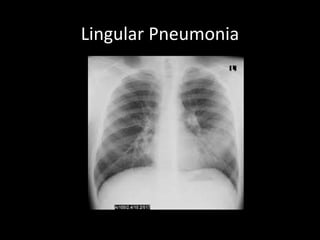

Lingular Pneumonia